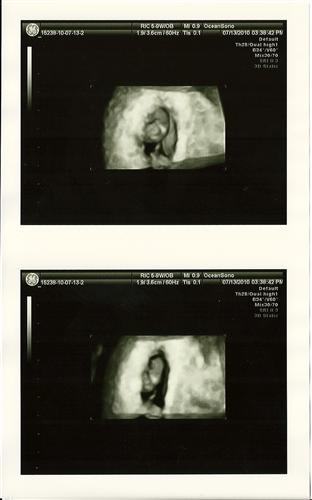

7w4d 3D

It looks like a face but the doctor told us that it wasn't. It's still really neat.

OMG those 3D pics from your 7 w 4d are amazing!!! :)